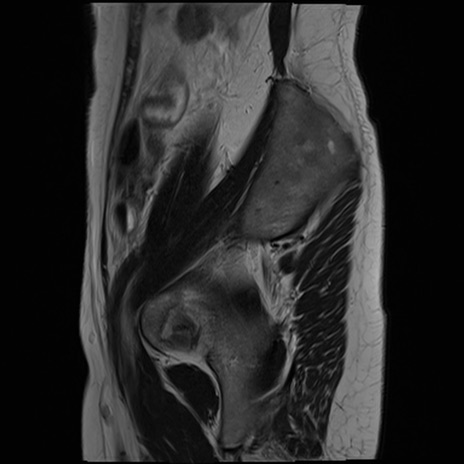

症例39 T2WI(矢状断像)

MRI(4日後)